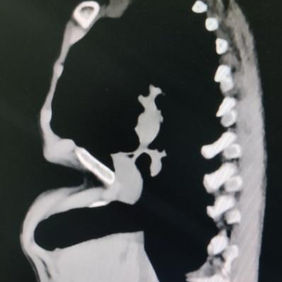

A severe depression is present in the center of the chest wall, with the right edge of the depression forming a ridge-like protrusion. Meanwhile, the edges and bottom of the depression have developed acute angle deformities.

Acute angle deformity refers to a specific type of localized deformity where a sharp angle forms in areas of significant protrusion or depression of the chest wall. This malformation does not exist independently but rather manifests as a feature within a diverse range of chest wall deformities, encompassing single deformity such as pectus excavatum and pectus carinatum, as well as various complex deformities.